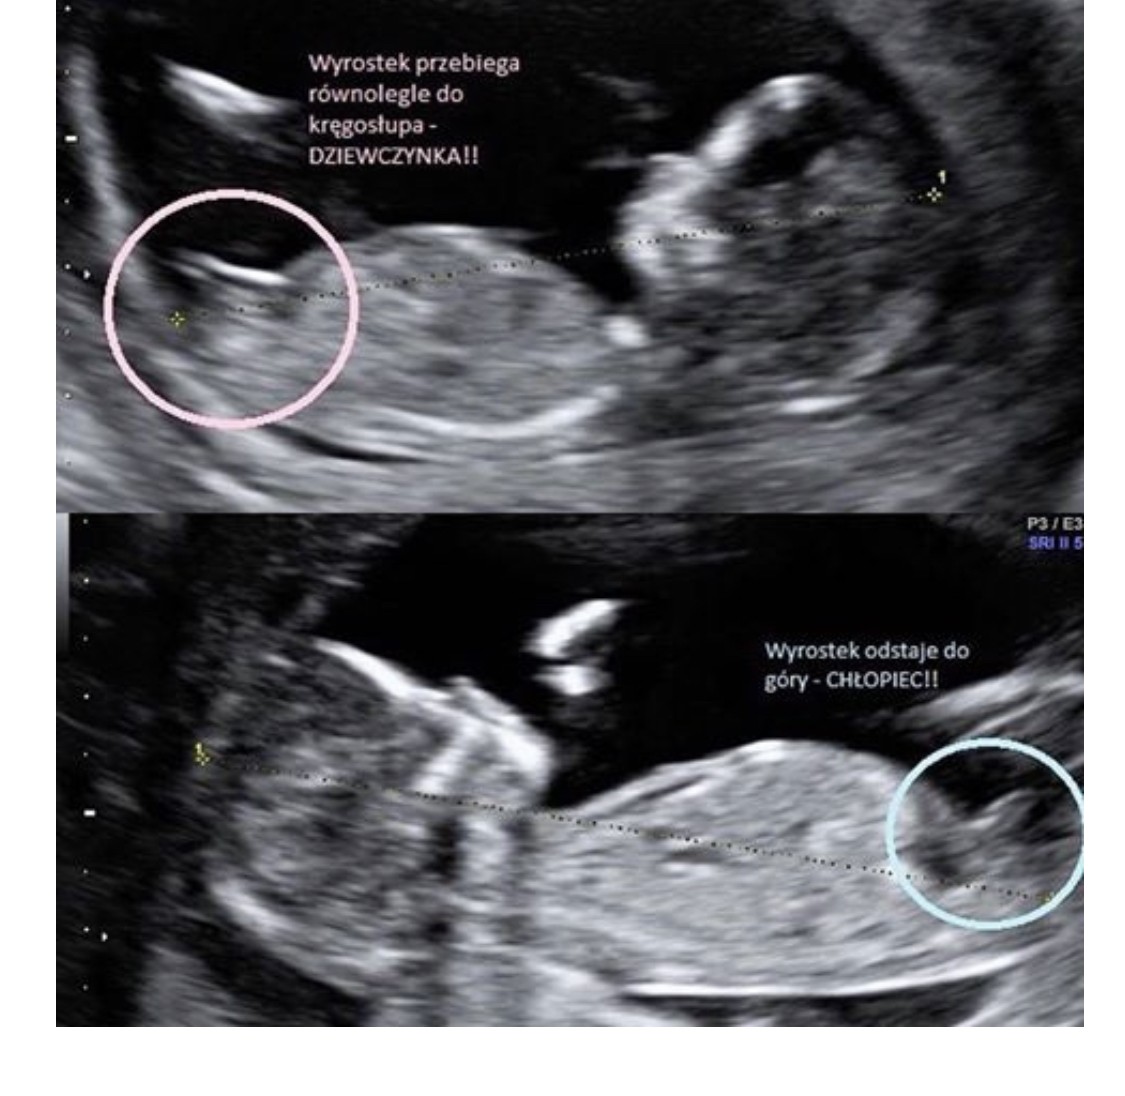

Muszę sprawdzić w dokumentach dokładnie, a te zostawiłam u teściówGdyby zdjęcie było z boczku zrobione to tak jak dziewczyny powyżej mówiły - wyrostek układa się przy chłopcu wzwyż, a przy dziewczynce bardziej rownolegle. Masz może inne zdjęcie?